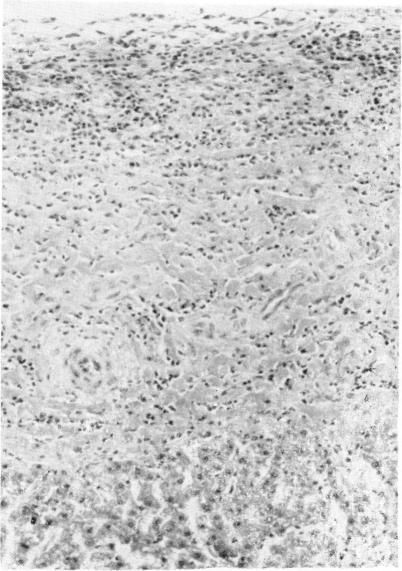

Six white-tailed deer (Odocoileus virginianus) and six sheep were inoculated with metacercariae of Fasciola hepatica. Two animals of each species were given 100, 500 or 2500 metacercariae. One animal in each inocluated group was killed and examined at six weeks postinoculation and the remainder at 15 weeks postinoculation. At six weeks postinoculation the parietal surface of the livers from inoculated deer was covered with gray fibrous plaques and rust colored patches. Fibroplasia with mononuclear cell infiltration characterized Glisson's capsule on the parietal surface. Granulomas were found in the hepatic parenchyma and on the dorsal surface of the lung. Fresh and healing tracks were occasionally found in the liver. In the sheep fibrinous exudate and numerous subcapsular tracks were found on both surfaces of the liver. Inflammatory changes in portal areas and numerous fresh and healing tracks in the hepatic parenchyma were prominent features. At 15 weeks postinoculation inflammatory changes in Glisson's capsule of inoculated deer were less marked than at six weeks but portal fibrosis and hyperplasia of bile duct epithelium were more advanced. A zone of hemorrhage surrounded ducts that contained mature F. hepatica in one deer. The livers from the sheep were rough, pitted and covered with fibrous tags and adhesions to the diaphragm and greater omentum were common. Hemorrhagic tracks were common in the sheep given 500 and 2500 metacercariae. Portal fibrosis and hyperplasia of bile duct epithelium were seen in the sheep (100 metacercariae) that harbored mature F. hepatica.

给六只白尾鹿(弗吉尼亚鹿)和六只绵羊接种肝片吸虫的囊蚴。每种动物中有两只分别接种100、500或2500个囊蚴。每个接种组中的一只动物在接种后六周处死并进行检查,其余的在接种后15周处死并检查。接种后六周,接种鹿的肝脏脏面覆盖着灰色纤维斑块和锈色斑点。脏面的Glisson囊表现为伴有单核细胞浸润的纤维组织增生。在肝实质和肺脏面发现肉芽肿。肝脏中偶尔可见新鲜的和正在愈合的虫道。在绵羊中,肝脏两面均发现有纤维蛋白渗出物和大量被膜下虫道。门管区的炎症变化以及肝实质中大量新鲜的和正在愈合的虫道是突出特征。接种后15周,接种鹿的Glisson囊的炎症变化不如六周时明显,但门管纤维化和胆管上皮增生更明显。在一只鹿中,含有成熟肝片吸虫的胆管周围有一个出血带。绵羊的肝脏粗糙、有凹痕,表面覆盖着纤维条带,与膈肌和大网膜粘连很常见。接种500和2500个囊蚴的绵羊中出血性虫道很常见。在携带成熟肝片吸虫的绵羊(接种100个囊蚴)中可见门管纤维化和胆管上皮增生。